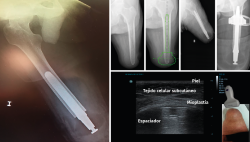

El implante femoral del estudio se compone de 3 piezas (Figura 2). El vástago femoral está fabricado de una aleación de titanio (Ti-6Al-4V) para facilitar el anclaje dentro del canal femoral. La segunda pieza es un espaciador fabricado en polietileno de alta densidad (UHMWPE) que se conecta distalmente con el vástago por mediación de la tercera pieza, un conjunto de tapón de polietileno y tornillo. El espaciador es el que permite el apoyo distal del muñón dentro del encaje.

Figura 2. Componentes del implante endomedular de carga distal Keep Walking®.

Figura 4. Estado final del implante Keep Walking® tras la cirugía y ecografía donde se aprecia la mioplastia distal de los tejidos blandos.

Las longitudes del vástago oscilan entre 120 y 180 mm, el diámetro de 11 a 17 mm y los diámetros de espaciador oscilan entre 54 y 62 mm. Finalmente, se monta el implante definitivo y se inserta impactado a press-fit en el fémur. Los tejidos blandos son suturados realizando una correcta mioplastia alrededor del espaciador (Figuras 4 y 5).